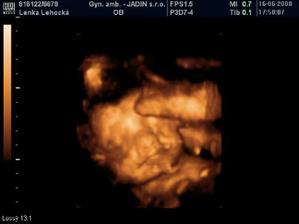

Ahojte.Volam sa Linda a na tento svet som prisla 25.9.2008 o 15.10 hod prirodzenym porodom..Merala som 49 cm a vazila 3450 g.Pri prepusteni z porodnice som mala sice o cosi menej,ale urcite to rychlo dobehnem.Maminke Lenke a ockovi Marianovi robim velku radost a tesia sa ze ma maju.